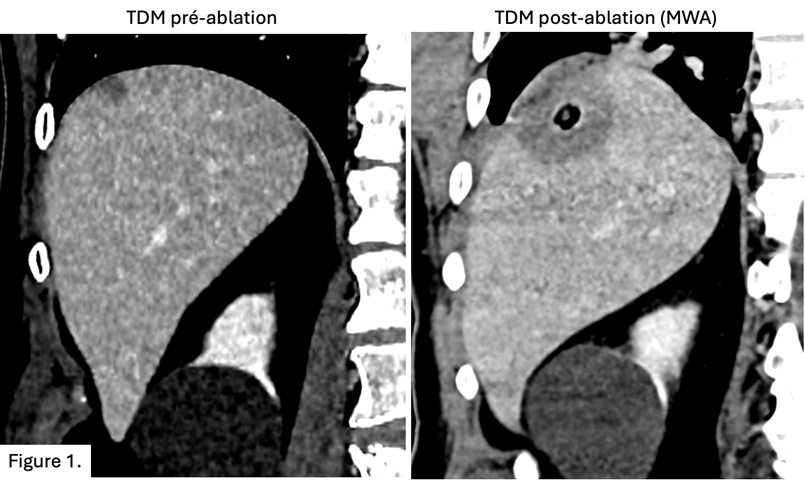

- Traitements mini-invasif des lésions tumorales : traitements intra-artériels, destructions tumorales percutanées